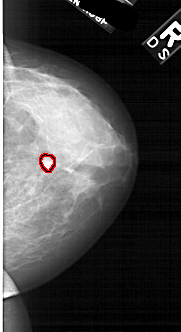

A_1877_1.LEFT_CC

LEFT_CC LINES 5416 PIXELS_PER_LINE 2506 BITS_PER_PIXEL 12 RESOLUTION 43.5 NON_OVERLAY

FILE: A_1877_1.RIGHT_CC.OVERLAY

TOTAL_ABNORMALITIES 1

ABNORMALITY 1

LESION_TYPE MASS SHAPE LOBULATED MARGINS CIRCUMSCRIBED

ASSESSMENT 4

SUBTLETY 3

PATHOLOGY BENIGN

TOTAL_OUTLINES 1

BOUNDARY